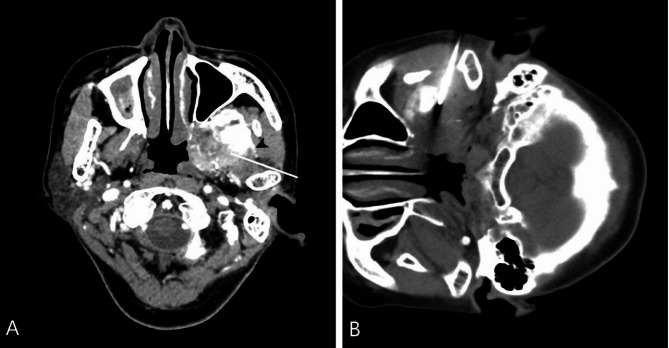

目的:舌骨上深部头颈部病变的病理诊断是重要的,组织取样需要平衡最小的侵入性和准确性。本研究的目的是评估ct引导下核心针活检(CNB)对舌骨上深部头颈部病变的诊断准确性和诊断失败相关因素。方法:回顾性分析204例ct引导下CNB患者的临床资料。ct引导下CNB采用18g同轴活检针进行病理诊断。病变诊断的准确性通过活检结果与手术标本的比较或根据治疗效果和6个月以上的临床随访来计算。通过卡方检验和程序特征和病变特征的logistic回归来确定与活检失败相关的因素。结果:所有204例标本均可用于组织学诊断,未发生立即或延迟的严重并发症。诊断敏感性为89.2%(141/158),特异性为97.8%(45/46),总体准确率为91.2%(186/204)。病变边界不清或术前诊断成像是诊断失败的潜在因素。结论:ct引导下的CNB是原发性舌骨上深部头颈部病变及颅底病变的有效组织诊断方法。值得注意的是,边缘不明确的病变和不理想的术前成像是导致诊断失败的潜在因素。具体来说,对于边界不清的病变,病变的范围难以划定,建议术前使用磁共振成像进行评估,以提高病变边缘的清晰度,从而有可能提高诊断的准确性。

Purpose: Pathological diagnosis is important for the treatment of deep suprahyoid head and neck lesions, and tissue sampling needs to balance minimal invasiveness and accuracy. The purpose of this study was to evaluate diagnostic accuracy and factors associated with diagnostic failure of core needle biopsy (CNB) with CT-guided in deep suprahyoid head and neck lesions.

Methods: The records of 204 patients who underwent CT-guided CNB were retrospectively reviewed. CT-guided CNB was conducted for pathological diagnosis with the use of 18-G coaxial biopsy needles. Diagnostic accuracy for the diagnosis of lesions were calculated by comparing the biopsy results with the operative specimen or based on treatment response and clinical follow-up more than 6 months. Factors associated with biopsy failure was identified by chi-square test and logistics regression of procedure characteristics and lesion features.

Result: All 204 specimens were deemed adequate for histological diagnosis, with no immediate or delayed severe complications encountered. The diagnostic performance showed a sensitivity of 89.2% (141/158), specificity of 97.8% (45/46), and overall accuracy of 91.2% (186/204). Respectively, lesions with poorly defined margins or pre-procedural diagnostic imaging were the potential factor for diagnostic failure.

Conclusion: CNB with CT-guidance is an effective procedure for tissue diagnosis of patient with primary deep suprahyoid head and neck lesions and skull base lesions. Notably, lesions with poorly defined margins and suboptimal pre-procedural imaging emerged as potential factors contributing to diagnostic failure. Specifically, for lesions with indistinct boundaries-wherein the extent of the lesion is difficult to delineate-pre-procedural assessment using magnetic resonance imaging is recommended to enhance the clarity of lesion margins, thereby potentially improving diagnostic accuracy.